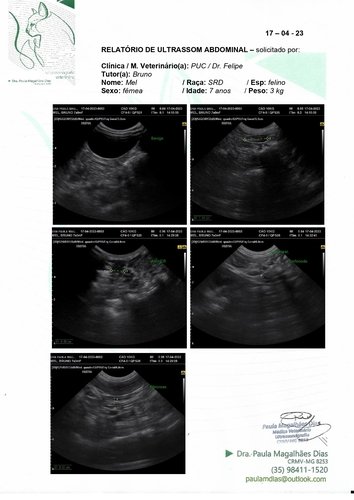

Olá, meu nome é Mel tenho 7 aninhos e peso 3kg (sim, sou bem pequinininha pra minha idade e comparado ao meu irmão de ninhada). Eu e meu maninho Cheetos fomos adotados pelo meu papai Bruno quando nossa antiga tutora faleceu. Nós ja tinhamos 2 aninhos na época, e nunca degrudamos um do outro nesses anos todos. Desde quando meu papai nos acolheu tínhamos que ficar separado da nossa irmã mais velha porque eu sempre fiz meu xixizinho em todo lugar que eu vejo, não faço na caixa de areia e nem mesmo cubro quando decido fazer lá. Mas nunca faltou carinho e amor independente de tudo. Recentemente papai e mamãe decidiram me levar no veterinario para ver o que seria esse problema de xixi em todo lugar, o doutor pediu ultrassom e infelizmente descobrimos a princípio um tumor bem grande perto da bexiga (o qual poderia ter deslocado minha bexiguinha e talvez possa explicar algumas coisas). O doutor disse que teríamos que fazer uma tomografia em outro estado pois onde moramos não tem, e pelas contas dos meus papais ia ficar mais de R$2000,00 fora a cirurgia ><. Mas o doutor disse que podemos ir direto pra cirurgia pra tentar solucionar e não alastrar mais o tumor. Quando chegamos para a cirurgia nao pude fazer por ter fugido do jejum porem me pediram pra refazer os exames e nisso apareceu que o que era um tumor parecia mais uma castração mal feita que tinha deixado partes do ovario e tava causando infecções. Meus papais vieram pedir ajuda pois a cirurgia vai ficar cara fora os medicamentos.

Vamos anexar aqui todas fotos, exame e valor da cirurgia! Qualquer ajuda é bem vinda e contamos com vocês pra logo logo eu ficar bem de novo e poder ficar grudada brincando com meus irmãozinhos!! <3